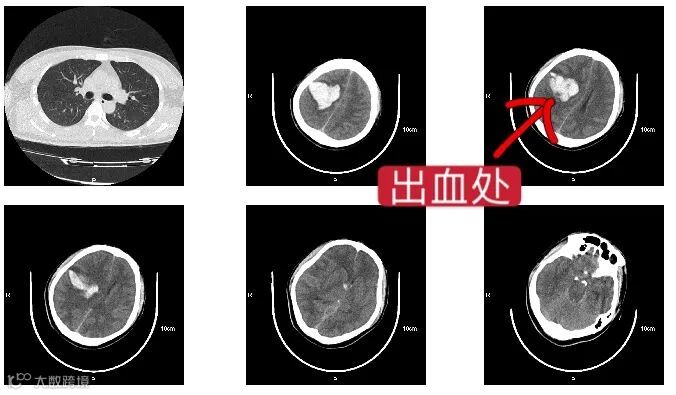

近日,一名27岁小伙因长期熬夜导致动脉瘤破裂被送到市人民医院,还好抢救及时,手术顺利,小伙现在进一步康复中。

头部CT检查提示,小谷是脑部动脉瘤破裂出血,手术后,小谷慢慢好转起来……

其实小谷的脑出血不是突然出现的,早在半个月前他就一直头疼,但他总是吃了止疼片就不去在意,继续工作,觉得自己还年轻,熬熬夜不会怎么样。